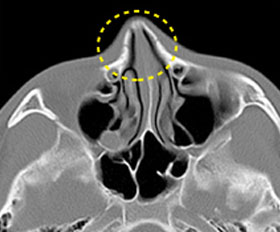

비중격만곡증

비중격이 휘어져 코막힘 등

Nasal septal curvature